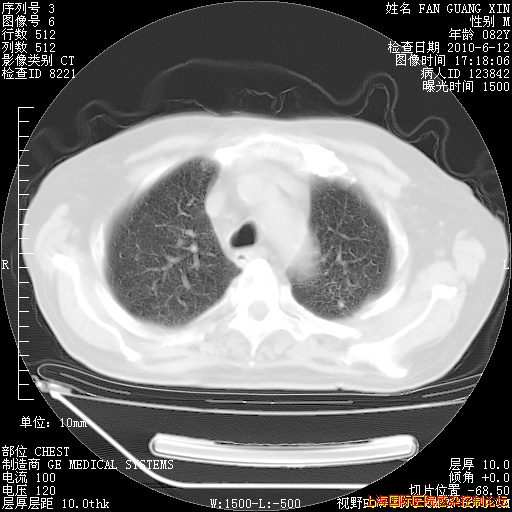

补发6月12日肺部CT肺窗

6月12日肺窗

整整相隔30天的肺部CT好像有所好转啊。甲强龙减量第3天,需要观察体温。

海管,自昨日你和我通完话后,不知您岳父消化道症状有无缓解?体温怎样?阅读7.12日胸部ct,个人认为目前激素治疗是有效的,甲强龙减量是适宜的。因在抗痨治疗,需密切观察肝功、肾功能和血常规。不过,老年、长期住院和大量使用激素,很担心菌群失调发生